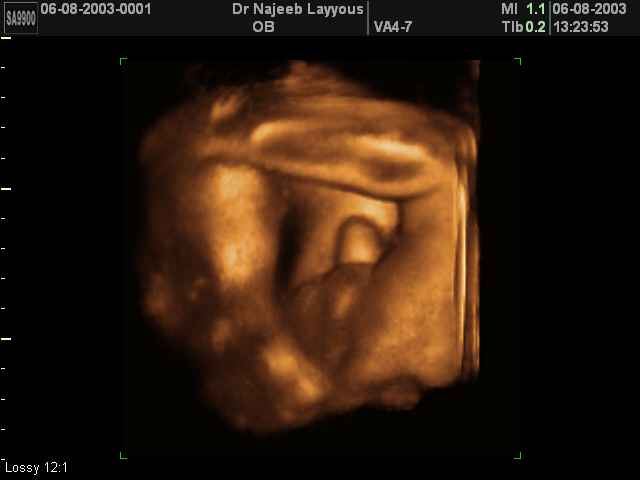

- 3D Photos échographie des parties du fœtus